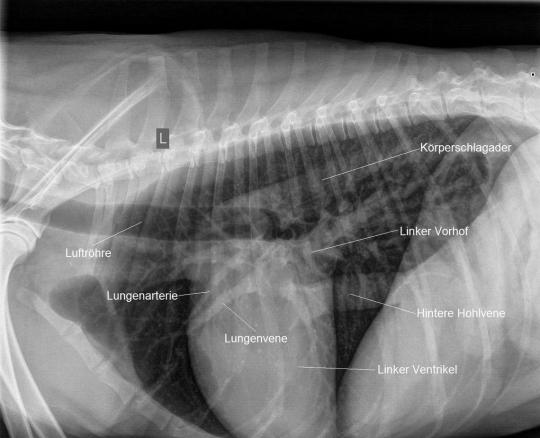

Radiologisch wird schnell klar, weshalb der Hund verstärkt atmet: Weite Teile der Lunge scheinen diffus verdichtet (d.h. weiss); Art und Verteilung der Veränderungen sprechen für eine Ansammlung von Flüssigkeit in der Lunge, ein Lungenödem. Die Herzsilhouette ist ausserdem vergrössert, insbesondere die linke Herzkammer und der linke Herzvorhof erscheinen erweitert.

Der Herzultraschall bestätigt den röntgenologischen Verdacht eines Herzproblems: Sowohl die Hauptkammer als auch der linke Vorhof sind bei Karammaz stark erweitert; die Kammer zieht sich ausserdem in der Pumpphase des Herzen zu wenig zusammen, wodurch das Organ zuwenig Blut fördern kann. Im Doppler-Ultraschall ist zu erkennen, dass durch die Erweiterung des Herzen auch die Klappen zwischen linkem Vorhof und linker Kammer undicht geworden sind und Blut beim Pumpen zum Teil nicht in den Körper, sondern zurück in den Vorhof gepumpt wird. Sonografisch ist also ein typisches Bild einer sogenannten Dilatativen Cardiomyopathie (DCM, Herzmuskelerkrankung, welche mit einer Erweiterung einhergeht) vorhanden; als Folge der geringen Pumpleistung des Herzen hat sich ausserdem ein Lungenödem gebildet.